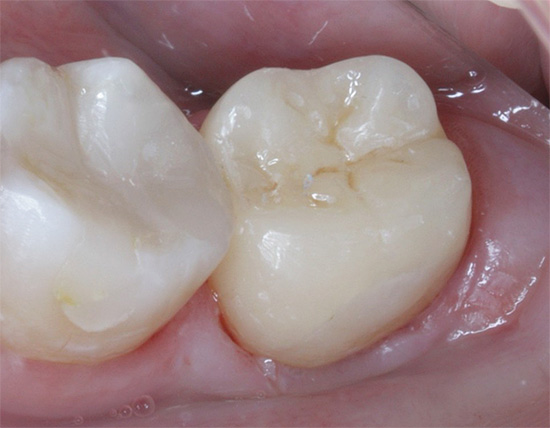

Foto de um dente de pulpite no início do tratamento e após a sua conclusão: